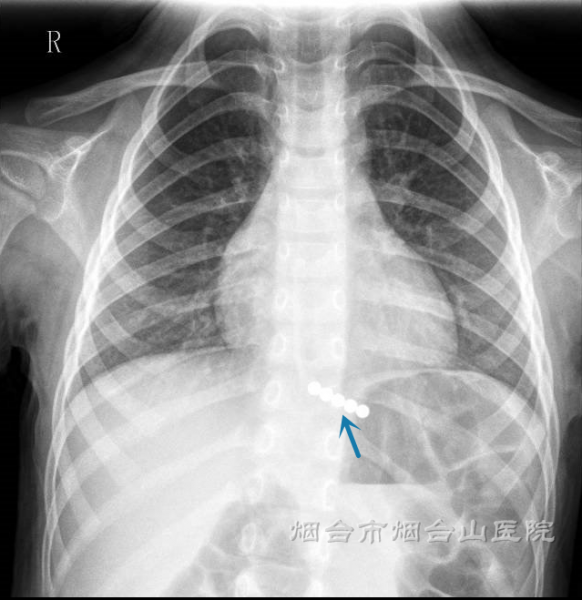

24日凌晨,倩倩的家长带她来到烟台山医院东院儿科急诊,急匆匆地告诉医生“孩子吞了磁力珠,不止一颗,现在肚子疼”。接诊的赵青春医生建议立即给孩子拍一个胸腹部立位平片。待拍片后,平片提示:磁力珠滞留在膈肌水平,食管下段,贲门口附近。磁力珠共计5颗,呈“一”字形排列。